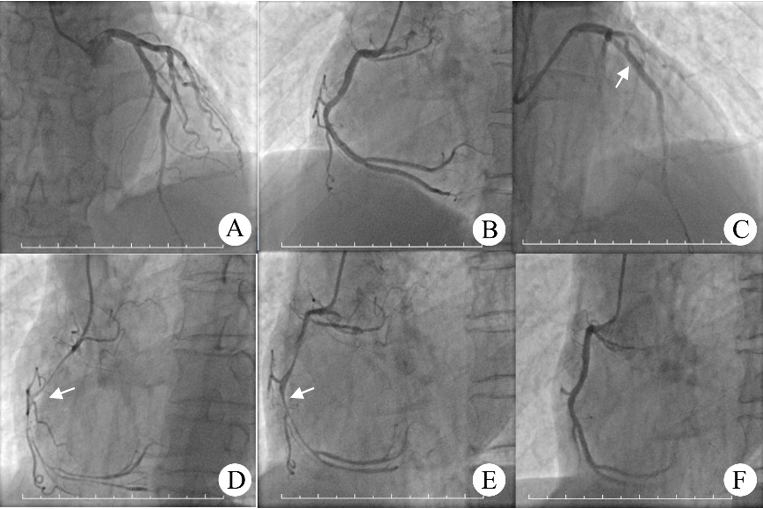

1.4 诊疗经过入院5 d后,患者行冠状动脉造影,1% 利多卡因局麻下右侧桡动脉穿刺置入6F血管鞘,造影剂为碘海醇(扬子江药业,国药准字H10970327,批号17011061)。5F TIG导管行冠状动脉造影示冠状动脉呈均势型;左冠状动脉主干未见异常,左前降支中段80% 狭窄,左回旋支近段不规则,远段50% 局限性狭窄;右冠状动脉中段40% 狭窄;三支血管前向血流均TIMI 3级(图 1A, 1B)。左前降支行经皮冠状动脉介入治疗,经3.5 EBU指引导管,送BMW Ⅱ导丝至左前降支远端,植入3.5 mm×28 mm DES支架于左前降支中段10 atm×5 s释放,后扩球囊3.5×12球囊支架内12~18 atm×5 s后扩后造影支架内无残余狭窄,前向血流TIMI 3级;拟结束手术尚未拔出桡动脉鞘管时,患者突然出现言语不清,述面部麻木,胸闷不适,伴恶心呕吐,见面色潮红,呼吸困难,喉中分泌物较多;经桡动脉鞘测有创动脉压为40/20 mmHg,心率40次/min;测氧饱和度70%;患者随即神志淡漠,出现躯干部皮肤潮红,双肺未闻及明显湿啰音;吸痰,面罩吸氧;同时予以甲泼尼龙琥珀酸钠40 mg,多巴胺5 mg、阿托品1 mg,随后再次静推地塞米松5 mg,心率快速上升, 窦性心律110次/min,胸导联及肢体导联无明显ST-T抬高。予以多巴胺联合间羟胺泵入升压,观察约15 min患者维持在50/40 mmHg左右,不能继续上升。复查冠状动脉造影提示左冠状动脉支架近端轻度痉挛,TIMI血流Ⅲ级(图 1C),右冠状动脉弥漫性严重冠状动脉痉挛,TIMI血流Ⅱ级(图 1D);冠状动脉内注射硝酸甘油100 μg无效后予以硝普钠10 μg×2次,恢复部分血流(图 1E),再予以硝酸甘油100 μg,右冠状动脉痉挛缓解,血流恢复正常(图 1F);血压开始回升至60/40 mmHg,持续予以多巴胺联合间羟胺泵入血压继续缓慢上升,再次予以地塞米松5 mg静推;50 min后患者血压逐步回升至90/60 mmHg,氧饱和度至92%,心率100次/min (窦性心律),胸闷改善,意识清晰,生命体征趋于稳定,转CCU监护治疗。予以补液扩容,继续升压第2天停用。第3天,双上臂及胸部散在分布的压之不褪色的红色皮疹显著减轻,双侧瞳孔对光反应迟钝状况显著恢复。查粪隐血试验+++;血常规:白细胞25.24×109/L,中性粒细胞比率83.04%,红细胞5.44×1012/L,血红蛋白173.00 g/L,血小板309.00×109/L。C反应蛋白2.00 mg/L。肾功能正常。电解质:钾3.30 mmol/L,余正常。心肌标记:肌酸酶同工酶4.50 ng/mL,肌钙蛋白I 0.05 ng/mL,肌红蛋白288.00 ng/mL。空腹血糖10.00 mmol/L,4 d后恢复正常出院。出院带药:阿司匹林50 mg,2次/d;氯吡格雷75 mg/d×14;兰索拉唑30 mg,2次/d;琥珀酸倍他乐克47.5 mg/d;瑞舒伐他汀钙片10 mg/d。甘舒霖30 R,早12 U-晚8 U,皮下注射,拜糖平50 mg,3次/d。随访3年,患者日常生活正常,无胸闷等不适,无其他过敏反应。

| A,B:左、右冠状动脉造影图片;C:冠状动脉介入治疗结束时过敏性休克血压不能维持复查冠状动脉造影,左冠状动脉前降支支架(箭头示)近端冠脉轻度痉挛狭窄;D:右冠状动脉弥漫性长程严重狭窄(箭头示);E:右冠状动脉内注射硝普钠后,冠状动脉痉挛状况逐渐缓解(箭头示);F:再次注射硝酸甘油后,右冠状动脉痉挛消失,恢复正常血流 图 1 冠状动脉DSA影像学改变 |